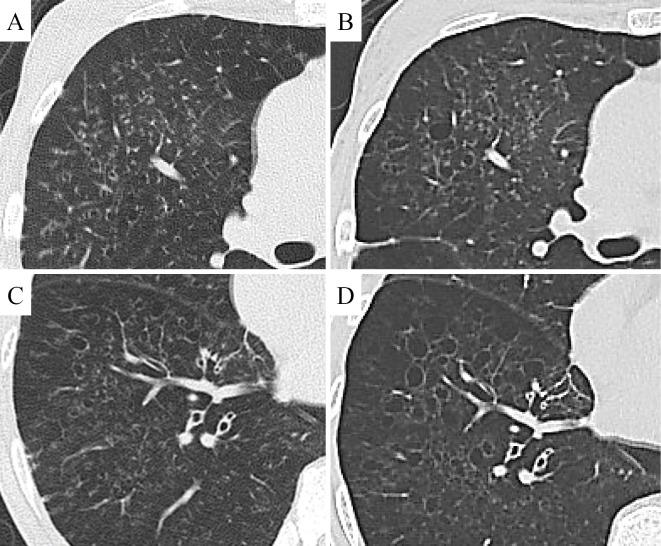

Idiopathic pulmonary hemosiderosis is characterized by repeated alveolar hemorrhaging. We herein report a 52-year-old Japanese woman who had shortness of breath, diffuse small nodules, thin-walled cysts, and bronchiolectasis. A surgical lung biopsy revealed peribronchial hemosiderosis, centrilobular emphysema, and fragile elastic fibers of the alveolar septa and small vessels. She ultimately underwent living-donor lung transplantation five years after the first visit.

特发性肺含铁血黄素沉着症的特征是反复肺泡出血。我们在此报告一例 52 岁日本女性,其症状为呼吸困难、弥漫性小结节、薄壁囊肿和支气管扩张。外科肺活检显示支气管周围含铁血黄素沉着症、小叶中心性肺气肿和肺泡隔及小血管脆弱的弹性纤维。她在首次就诊五年后最终接受了活体供肺移植。